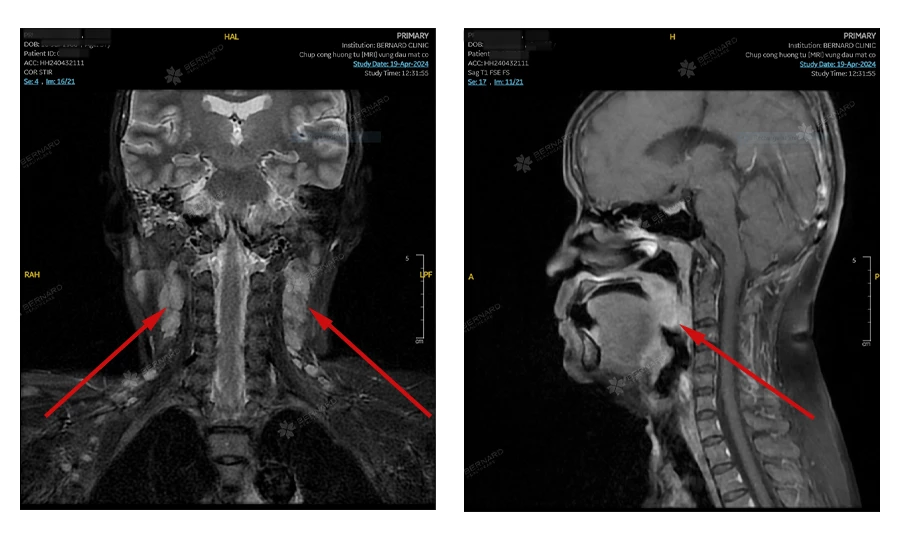

Bệnh nhân được tư vấn tiếp tục thực hiện chụp MRI để đánh giá mức độ lan rộng và khả năng xâm lấn của tổn thương.

Kết quả cho thấy: Tổn thương choán chỗ lớn lan rộng khoang niêm mạc hầu vùng khẩu hầu-tỵ hầu hai bên ưu thế phải, bờ giới hạn không rõ, kích thước # 25x45x70mm (trước sau x ngang x cao), tổn thương có dấu hiệu xâm lấn đáy lưỡi hai bên. Ngoài ra, còn có nhiều hạch cổ lớn (đường kính tối đa 2.3 cm), cho thấy có khả năng di căn hạch.